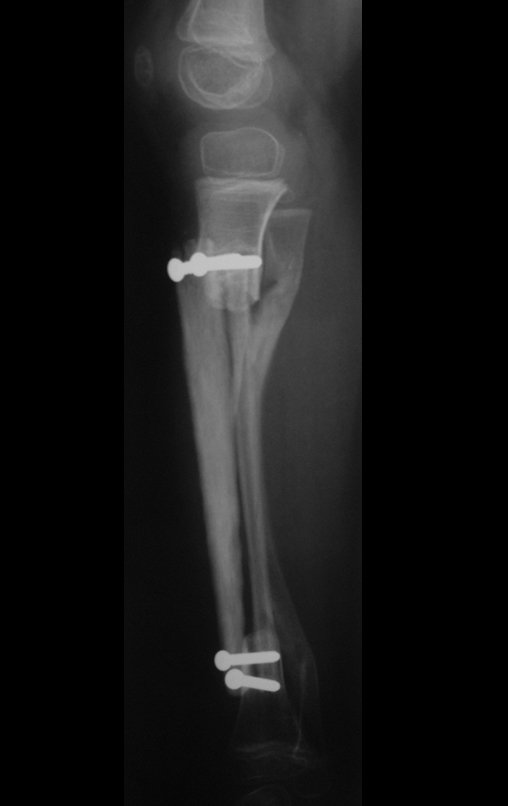

Osteofibrodysplasia – Fibula tibialization technique – Combined autologous and homologous graft reconstruction technique

The patient returns to the office six weeks after surgery, figures 100 to 102 and video 1